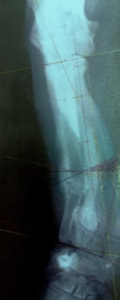

左後肢の完全挙上を主訴に来院されました。触診にて近位足根関節の過伸展を、レントゲン検査にて左足根関節周囲の軟部組織の腫脹、ストレス撮影によって距骨・踵骨と第4足根骨・中心足根骨間の脱臼および過伸展を認めました。

術前側面像屈曲位

術前側面像伸展位